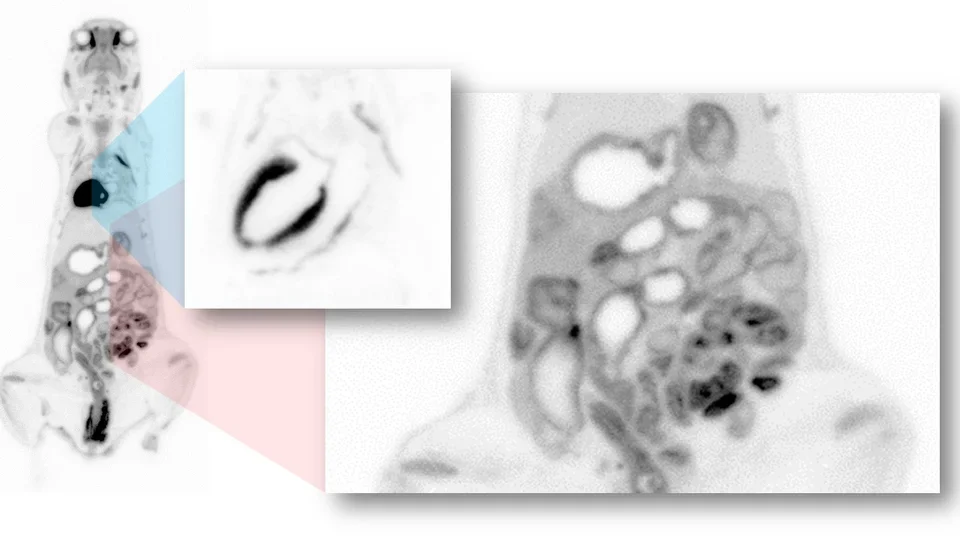

Single photon emission computed tomography (SPECT) imaging is a three-dimensional nuclear medicine imaging technique that enables real-time in vivo imaging to measure biodistribution of tracers, labeled novel compounds or cells. Our preclinical SPECT system (Mediso nanoScan SPECT/CT) combines an array of four gamma cameras on a gantry that rotate around the subject to provide spatial information on the distribution of the radionuclide within tissues. Common SPECT imaging applications include 99mTc sestamibi myocardial perfusion studies, 99mTc-HMPAO brain imaging to assess cerebral blood flow, 99mTc sestamibi parathyroid scans, 111In oxine-labeled white blood cell scans, 99mTc-methylene diphosphonate (MDP) bone scans, and biodistribution profiling of 177Lu- or 131I-labeled radioligand therapeutic agents.

nanoScan SPECT/CT (Mediso)

Positron emission tomography (PET) provides the means for imaging the rates of biologic processes in vivo. Imaging is accomplished through the integration of two technologies, the tracer kinetic assay method and computed tomography (CT). The tracer kinetic assay method employs a radiolabeled biologically active compound (tracer) and a mathematical model that describes the kinetics of the tracer as it participates in a biological process. The model permits the calculation of the rate of the process. The tissue tracer concentration measurement required by the tracer kinetic model is provided by the PET scanner, with the final result being a three-dimensional (3-D) image of the anatomic distribution of the biological process under study.

GNEXT PET/CT (Sofie Biosciences)